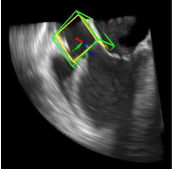

利用2891次心脏超声检查的数据集,Ghesu等结合深度学习和边缘空间学习进行医学图像检测和分割[12]。“大参数空间的有效探索”和在深度网络中实施稀疏性的方法相结合,提高了计算效率,并且与同一组发布的参考方法相比,平均分割误差减少了13.5%,八位患者的检测结果如图4所示。Brosch等人利用MRI图像上研究多发性硬化脑病变分割的问题。开发了一种3D深度卷积编码器网络,它结合了卷积和反卷积[13],图5.增加网络深度对病变的分割性能的影响。卷积网络学习了更高级别的特征,并且反卷积网络预进行像素级别分割。将网络应用于两个公开的数据集和一个临床试验数据集,与5种公开方法进行了比较,展现了最好的方法。Pereira等人的研究中对MRI上的脑肿瘤分割进行了研究,使用更深层的架构,数据归一化和数据增强技巧[14]。将不同的CNN架构用于肿瘤,该方法分别对疑似肿瘤的图像增强和核心区域进行分割。在2013年的公共挑战数据集上获得了最高成绩。

图4示例图像显示了不同患者的检测结果从测试集。检测到的边界框以绿色显示,标准的框以黄色显示。原点位于每个框中心的线段定义相应的坐标系